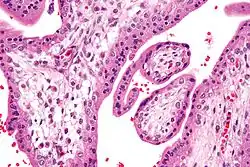

Chorionvilli (H&E-kleuring) -

Chorionvilli zeer sterke vergroting. (H&E-kleuring) -